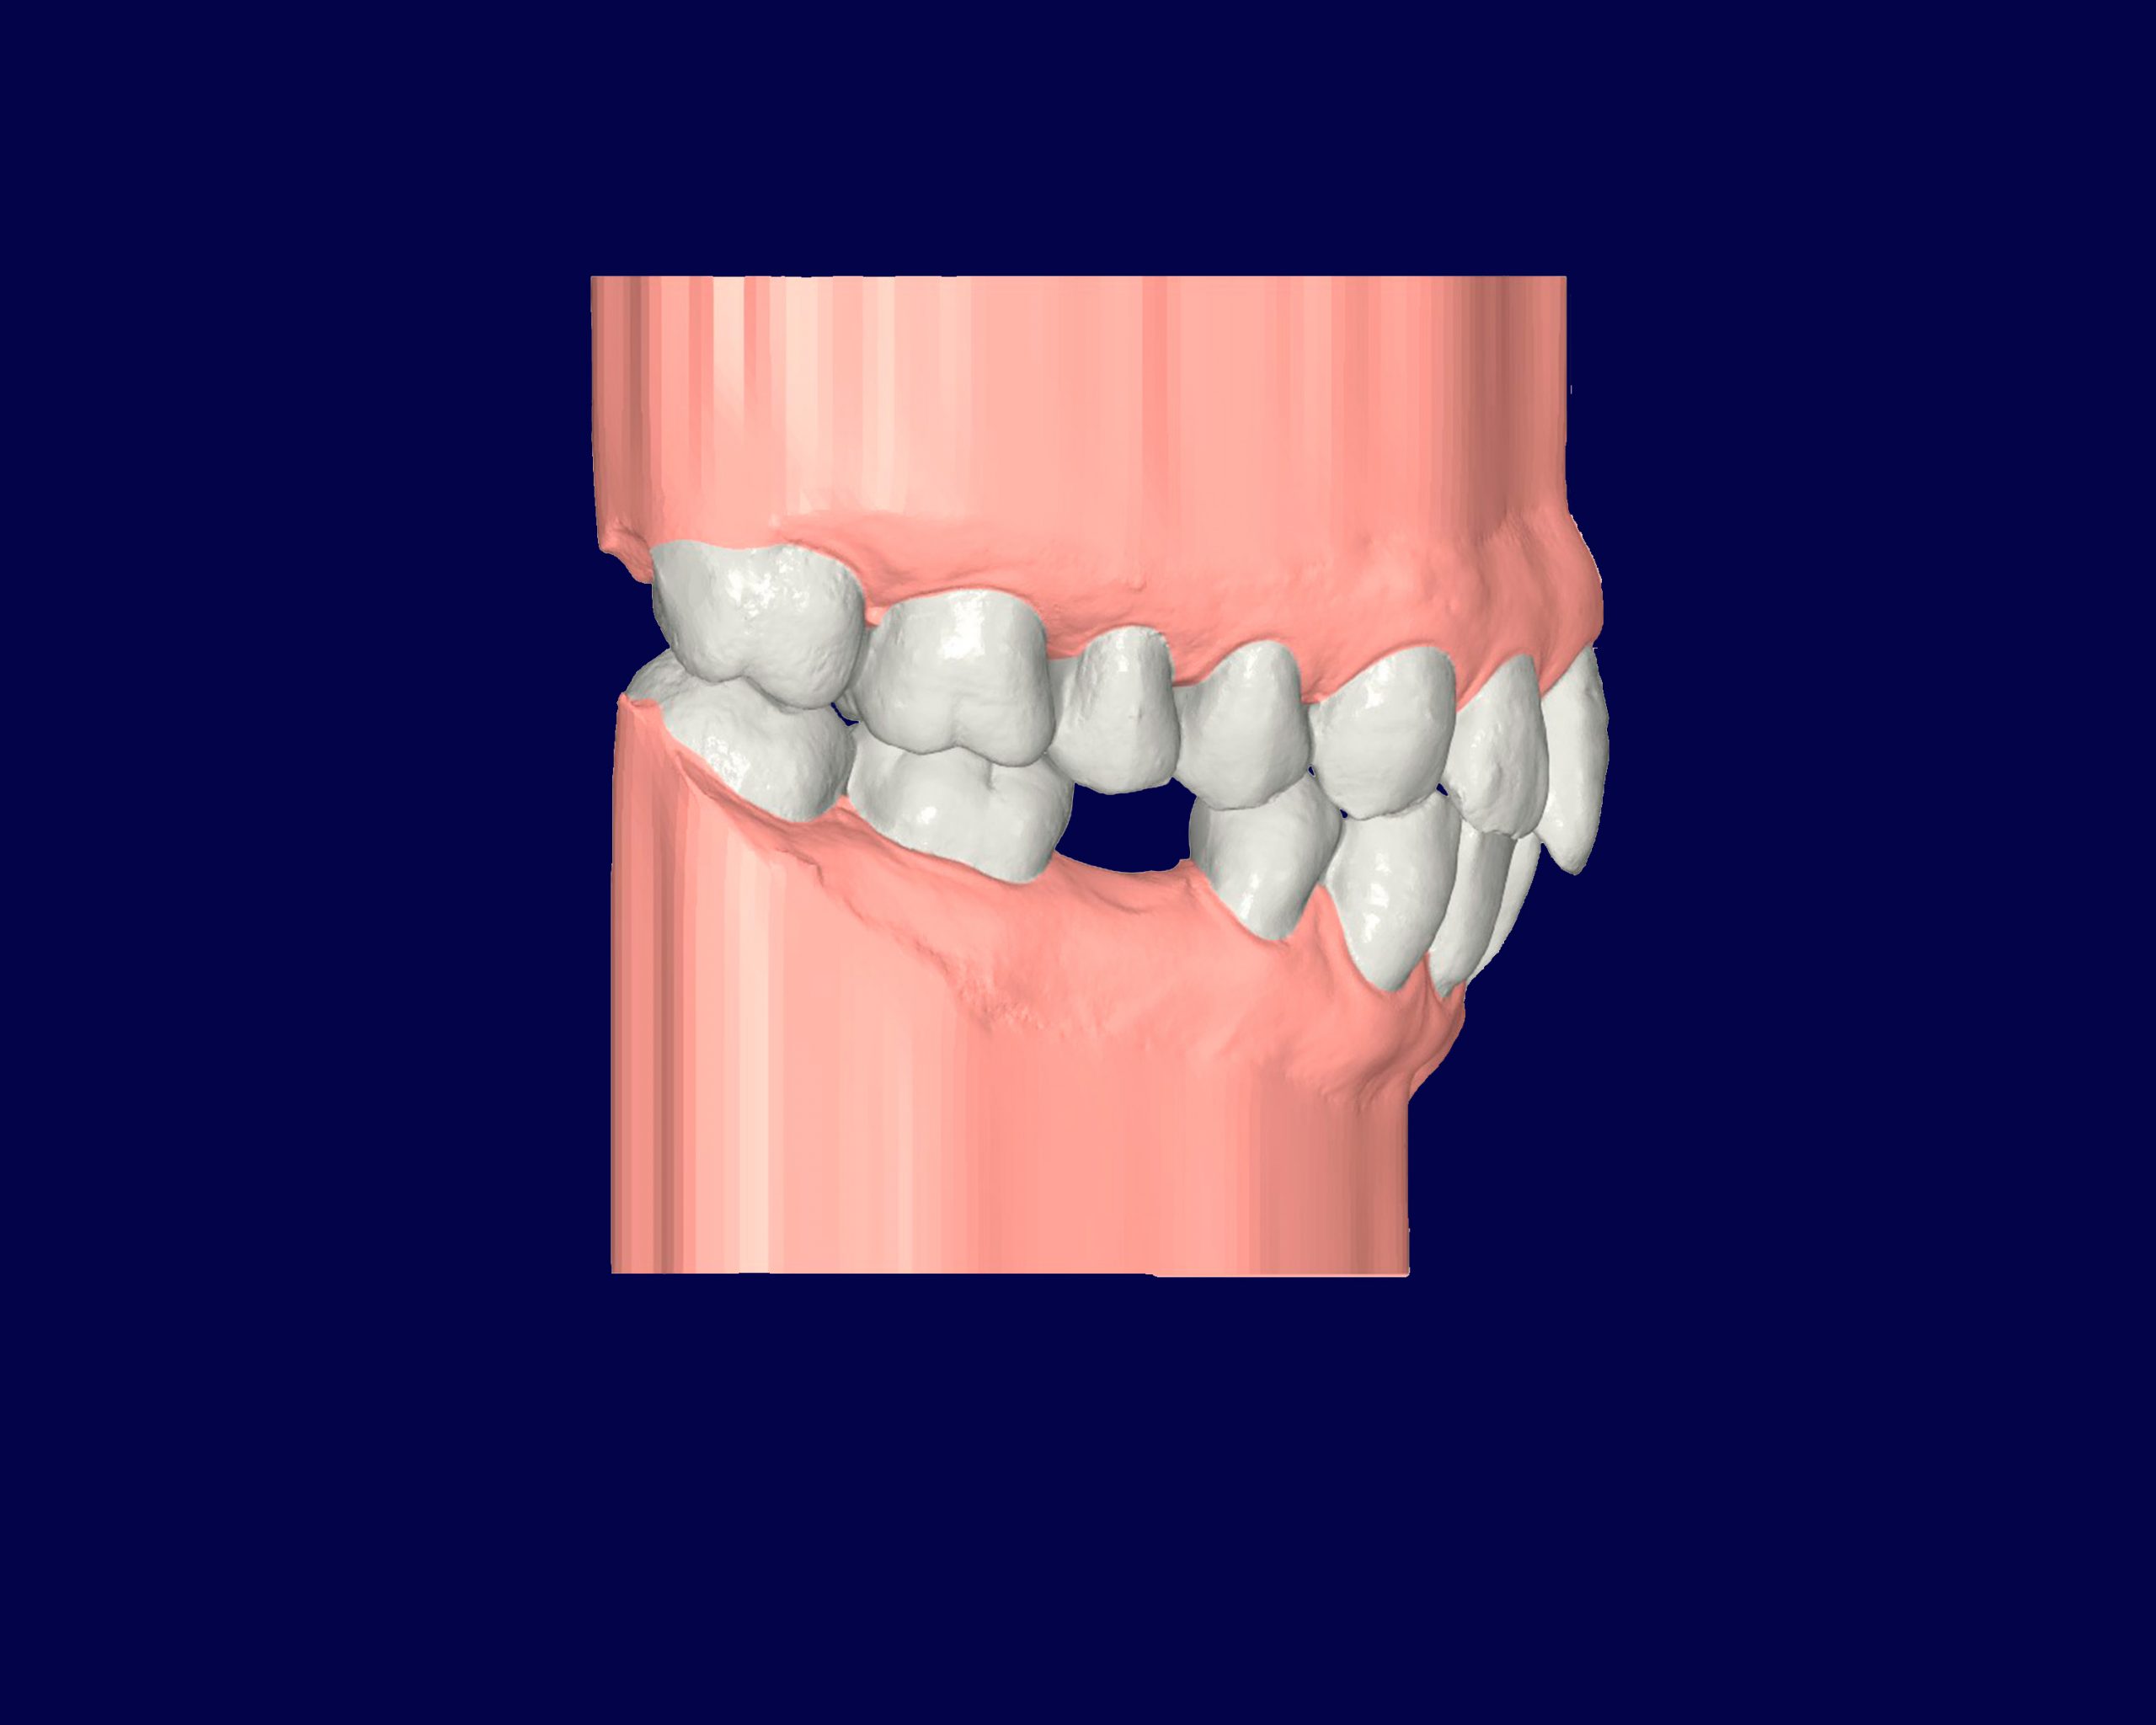

Mordida Cruzada

La mordida cruzada es una maloclusión en la que los dientes superiores muerden por dentro de los dientes inferiores, lo que puede afectar tanto la función masticatoria como la estética.

Esta condición puede generar desgaste dental, dolor en la mandíbula y problemas en el alineamiento facial